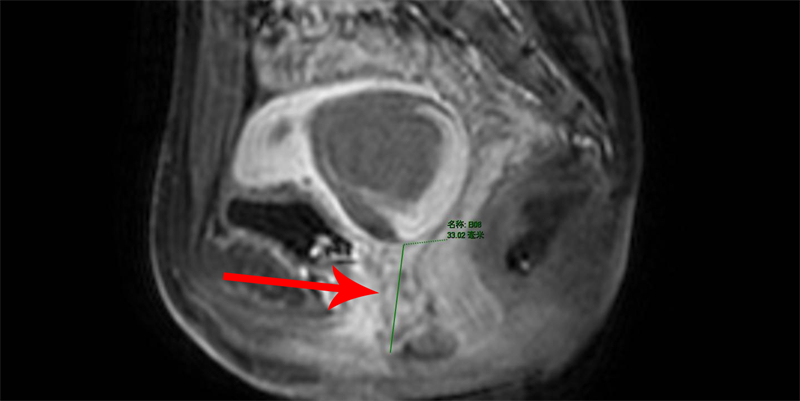

入院后,小佳進(jìn)一步完善了盆腔磁共振檢查,結(jié)果提示:宮頸管明顯擴(kuò)張,范圍為5.3cmx4.9cmx4.6cm,子宮內(nèi)膜未見明顯增厚,未見正常的陰道結(jié)構(gòu)、形態(tài)顯示,考慮宮腔積血、陰道閉鎖可能,結(jié)合小佳的病史既往無月經(jīng)來潮,明確診斷引起小佳腹痛的“真兇”為“陰道閉鎖”。

磁共振提示下段陰道閉鎖長度為33mm

醫(yī)生告訴小佳,她所患的是I型陰道下段閉鎖,子宮里的經(jīng)血無法經(jīng)過陰道排出體外,便聚集在陰道上段和子宮內(nèi),通過磁共振影像可以看到,她的陰道上段被大量積血充滿,像一個(gè)鼓鼓囊囊的“氣球”,這也是她為什么會(huì)下腹痛的原因。